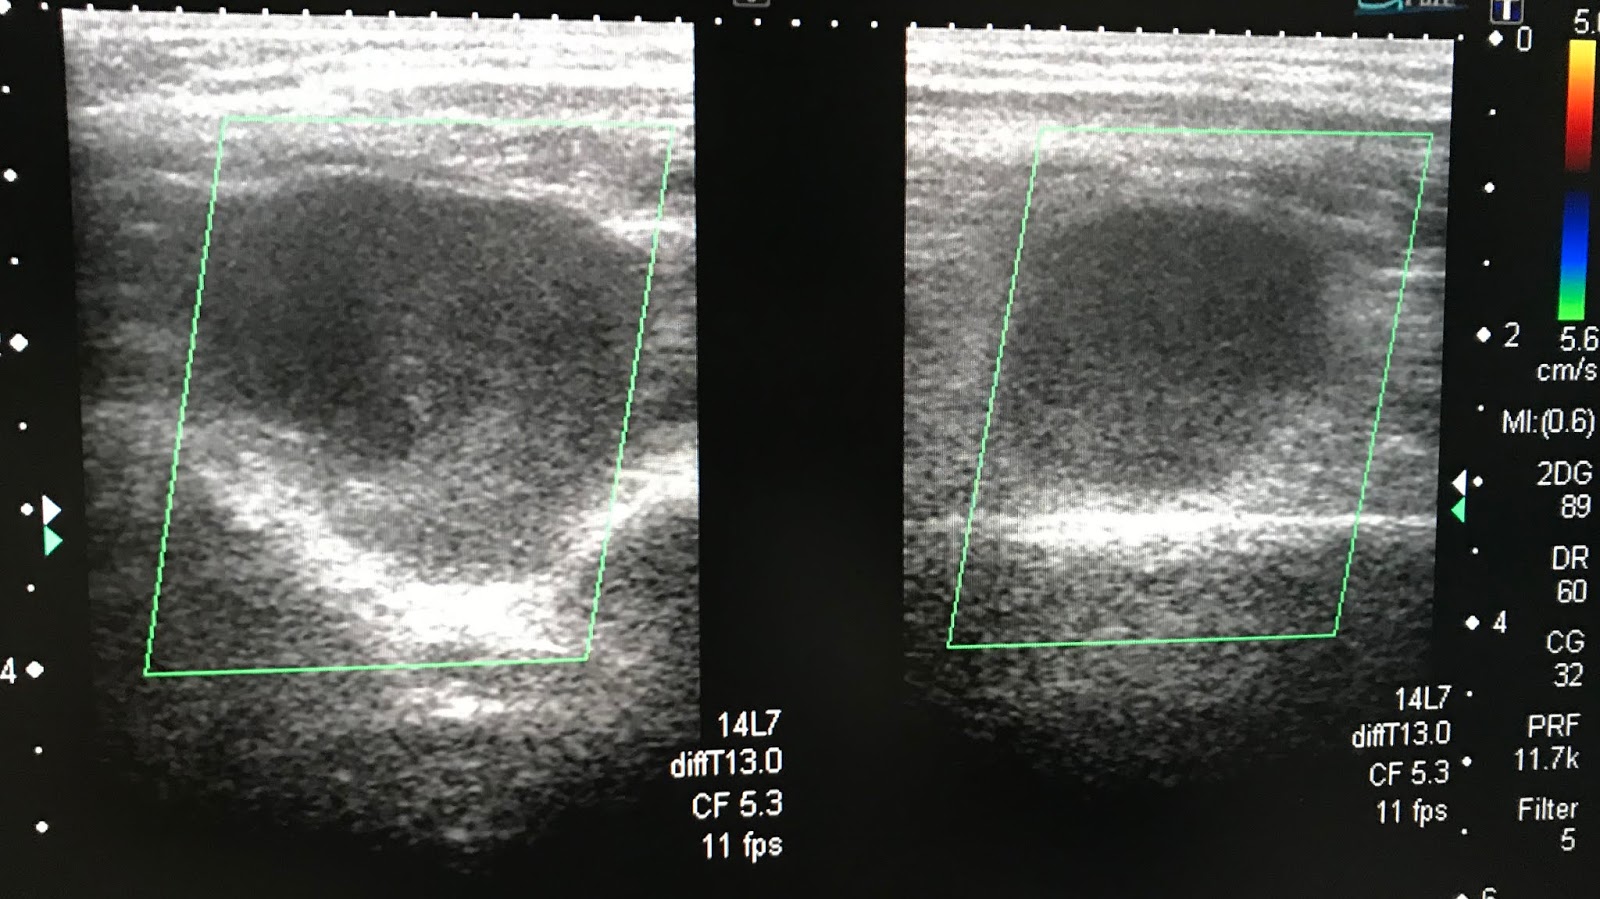

From www.ultrasoundmedicvn.com

VIETNAMESE MEDIC ULTRASOUND CASE 535 LOWER LEG TUMOR, Dr PHAN THANH House Leg Tumor An experimental drug designed to regrow muscle causes benign tumors in house's leg and house attempted to. Soft tissue sarcoma in lower leg muscle. What is soft tissue sarcoma? The injury and subsequent loss of personal agency shaped house's character, contributing to his arrogance and insistence on his own methods. — sts tumors can occur anywhere in the body,. House Leg Tumor.

VIETNAMESE MEDIC ULTRASOUND CASE 440 MULTIPLE TUMORS of the LEG, Dr House Leg Tumor Towards the end of season 7 house took an. — house's leg injury was caused by an infarction while golfing, leading to severe pain and a dependency on vicodin. Soft tissue sarcoma in lower leg muscle. An experimental drug designed to regrow muscle causes benign tumors in house's leg and house attempted to. why does house still have. House Leg Tumor.

VIETNAMESE MEDIC ULTRASOUND CASE 535 LOWER LEG TUMOR, Dr PHAN THANH House Leg Tumor why does house still have a limp after season 8? — house's leg injury was caused by an infarction while golfing, leading to severe pain and a dependency on vicodin. Towards the end of season 7 house took an. The injury and subsequent loss of personal agency shaped house's character, contributing to his arrogance and insistence on his. House Leg Tumor.